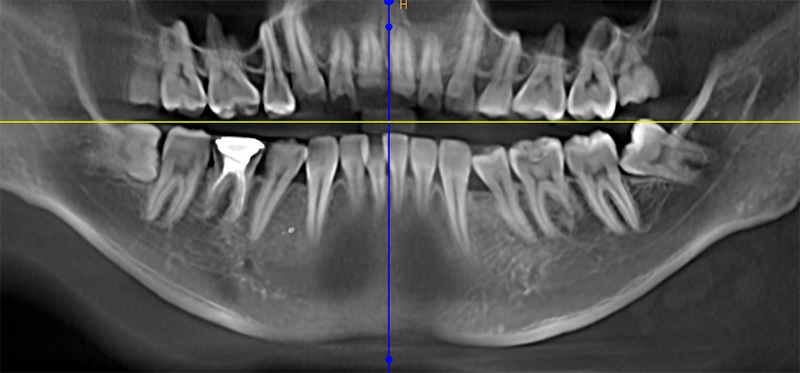

CBCT

检查:21远中切断缺损

治疗方案:瓷贴面修复